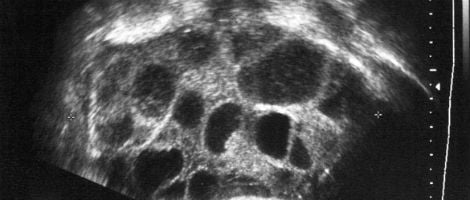

- A punção e aspiração folicular faz diminuir a gravidade do SHO.